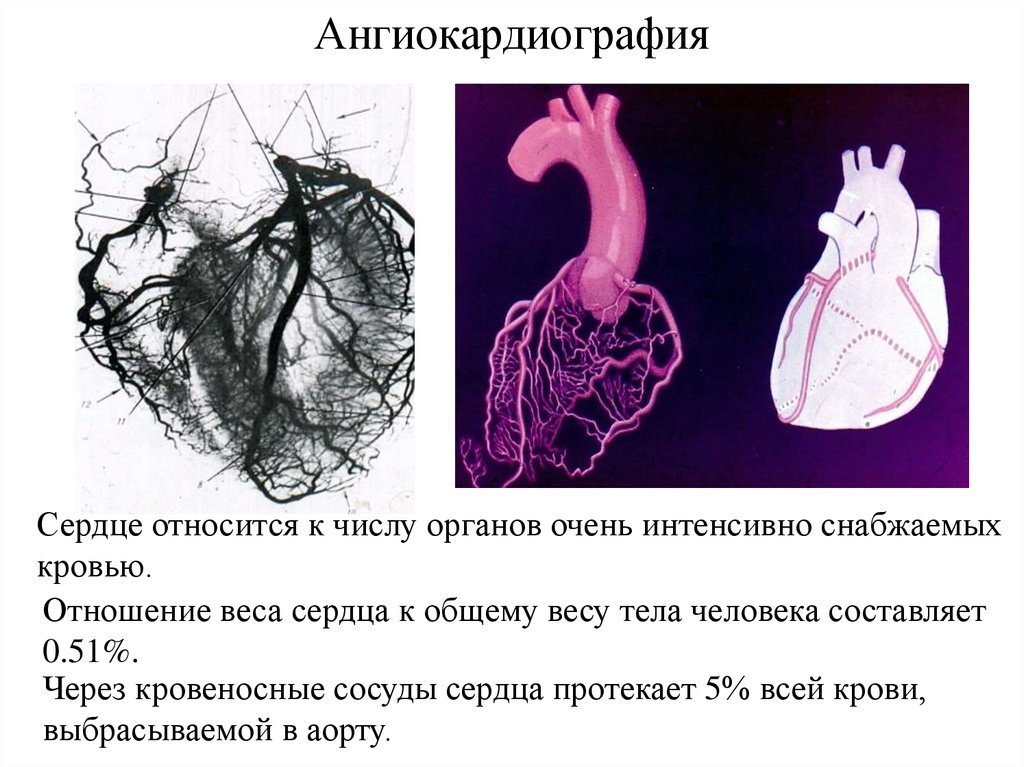

Раздел: Снимки успеха